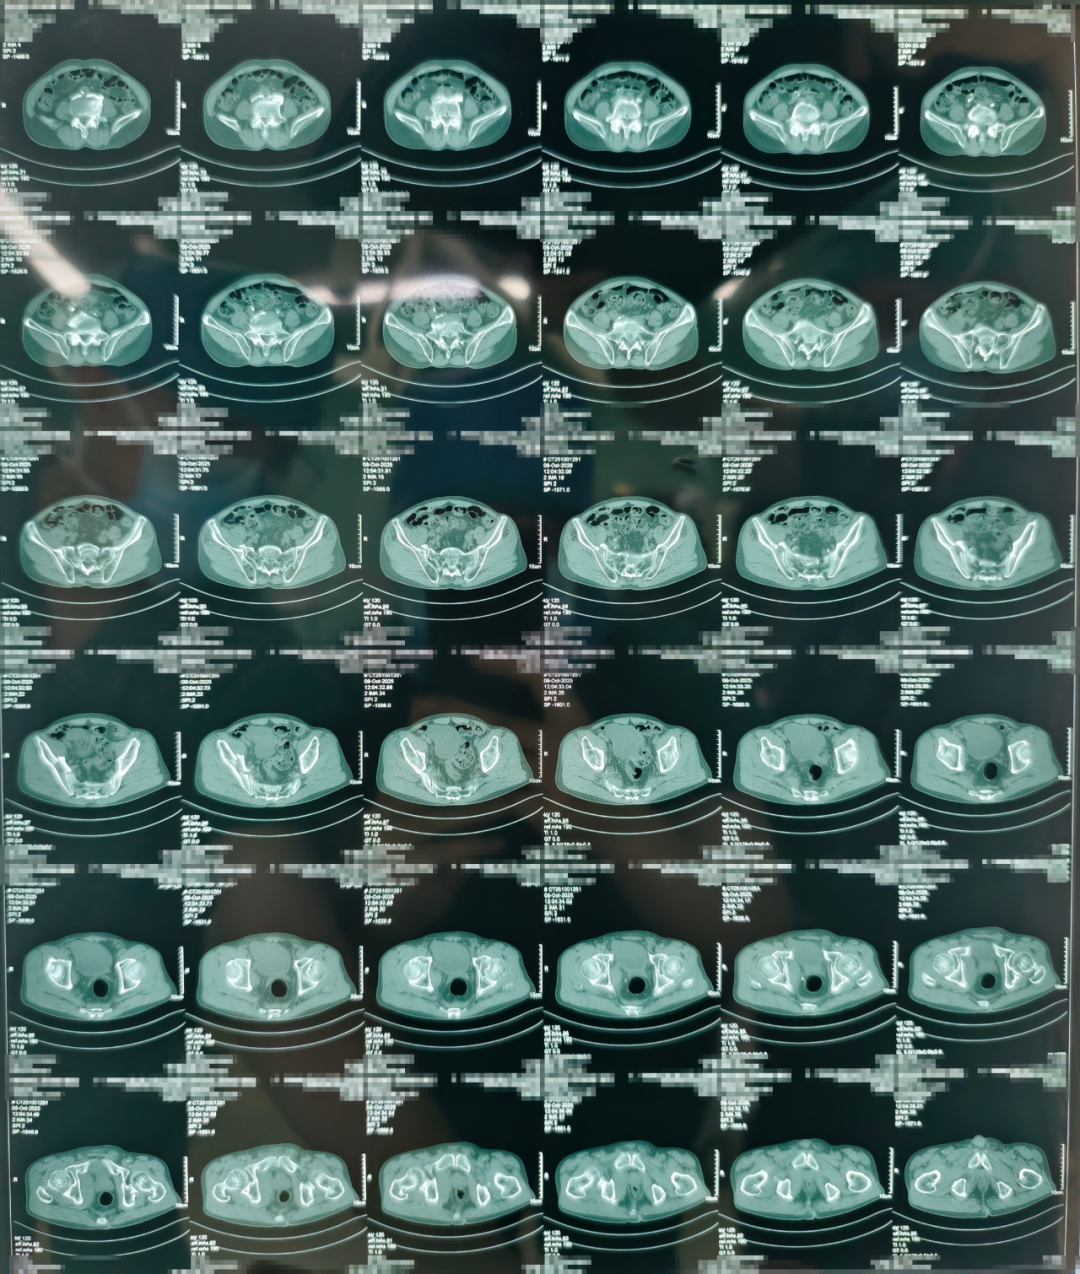

术前

团队通过三维影像重建,为患者量身定制手术路径,数据导入系统后生成个性化复位方案。

此次接受手术的七旬老人,因干活时不慎从自驾车摔落,导致全身多部位骨折,其中包括胸椎压缩性骨折、腰椎压缩性骨折、髂骨骨折、骶骨骨折、尾骨骨折、耻骨骨折、坐骨骨折。因骨盆结构复杂、周围血管神经密集,骨盆骨折素有“创伤之王”之称。面对患者骨盆多处骨折、血红蛋白偏低、传统手术可能带来较大创伤和出血风险等难题,贾长军主任团队果断选择借助最新引进的骨科手术机器人,制定个性化微创手术方案。